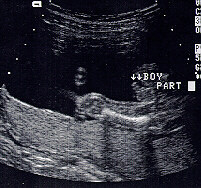

الولد

ولد في الأسبوع ال 15

ولد في الاسبوع ال16

الأسبوع ال17

الأسبوع ال18